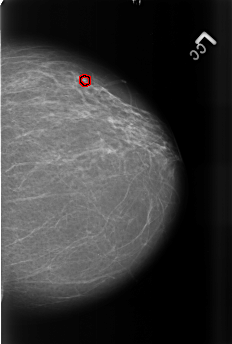

Digital Database for Screening Mammography

Volume: benign_14 Case: B-3467-1

B_3467_1.LEFT_CC

LEFT_CC LINES 4472 PIXELS_PER_LINE 3016 BITS_PER_PIXEL 12 RESOLUTION 50 OVERLAY

FILE: B_3467_1.LEFT_CC.OVERLAY

TOTAL_ABNORMALITIES 1

ABNORMALITY 1

LESION_TYPE CALCIFICATION TYPE PUNCTATE-PLEOMORPHIC DISTRIBUTION CLUSTERED

ASSESSMENT 4

SUBTLETY 3

PATHOLOGY BENIGN

TOTAL_OUTLINES 1